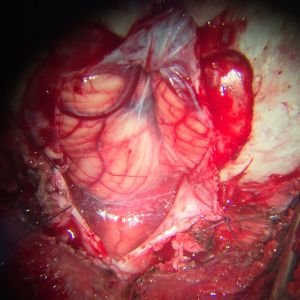

MEDULOBLASTOMA

DESCRIPCIÓN